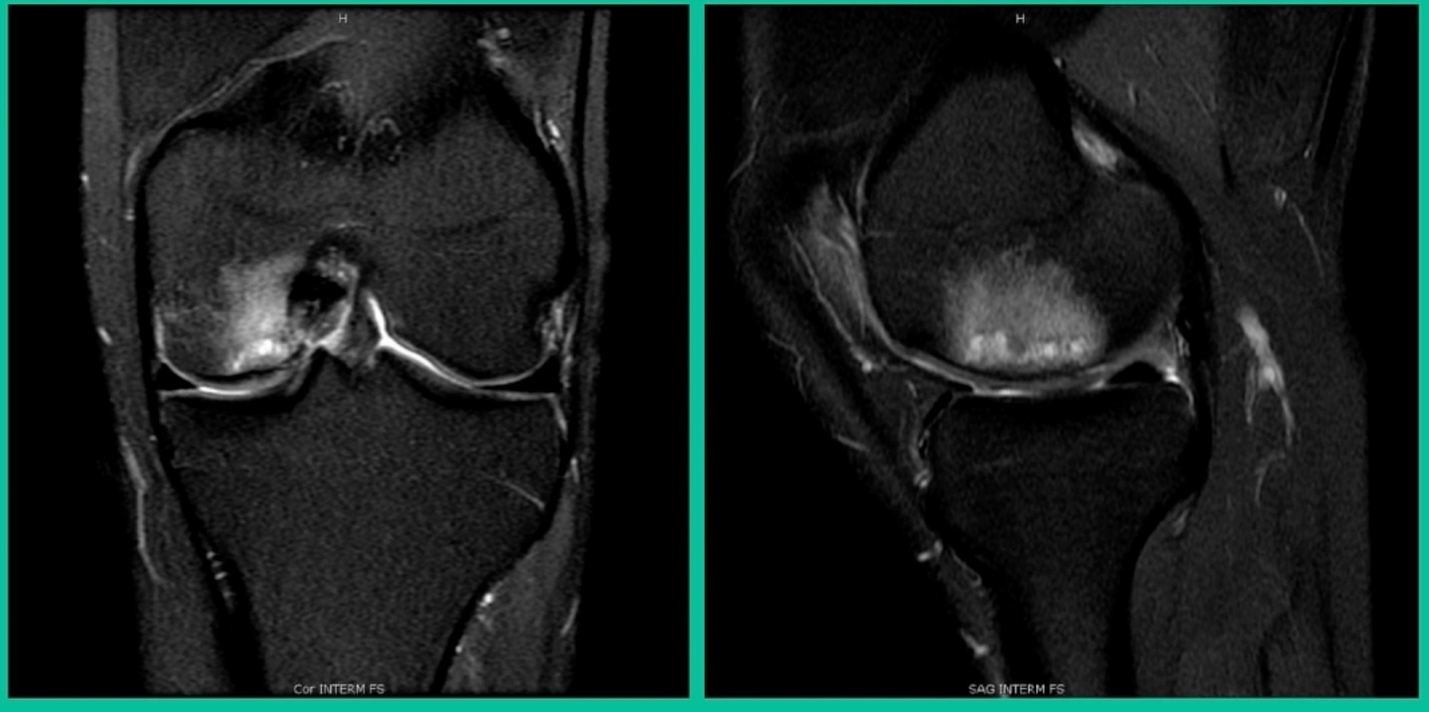

The last problem is we do occasionally see these in the tibia, and fortunately, we have solutions for the tibia. What did I do early on? This is a 15-year-old male runner.

Lateral knee pain and swelling, failed microfracture the tibia and so we did biocartilage.

This is basically lyophilized collagen taken from allogeneic cartilage, and we put it in arthroscopically with some fibrin glue. Then we did a subchondroplasty. That was my early treatment. Now, we’ve evolved. What do we do?

This is another one. 38-year-old, lateral side knee pain, lots of edema.

What’s amazing with this one is he’s got that little focal defect, but tremendous edema there and lots of bone pain. This one, we did something called AutoCart™ (Arthrex, Inc.).

Now, it’s an interesting procedure, and it’s sort of a poor person’s cartilage transplant. We take advantage of the body’s innate ability to heal. That’s the lateral tibial plateau and we’re curating the base of it. Using a shaver we grab cartilage from the intercondylar notch and we collect it in a little receptacle (that’s collecting the cartilage).

We then make this sort of “witches’ brew” of articular cartilage, which is living articular cartilage, some collagen, what we call bio cartilage as a scaffold, and bone marrow concentrate, and then we create a paste. Then, arthroscopically, we introduce it, and we put fibrin glue over it. Then, to treat the edema, we do something called OssioFix or KneeBar (Ossio Inc.) where we take a biocomposite pin. It’s like a rafter screw, and we put it across the tibia to shore up the tibia. We have now about 20 patients who have been treated this way and it can be very good because we’re treating the bone and the cartilage.